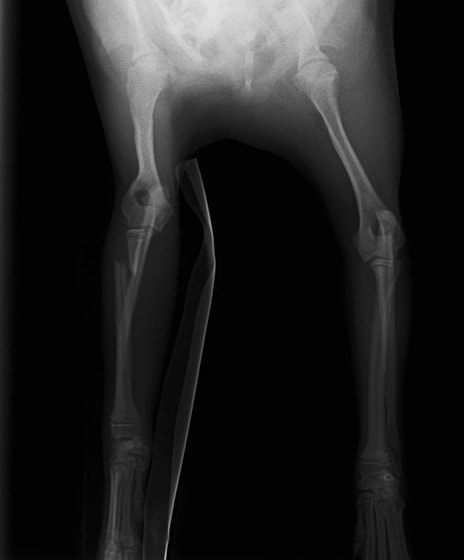

症例3:キルシュナーワイヤーのピンニングによる整復

ペルシャ猫 11ヶ月齢 雄

他院にて左大腿骨遠位の成長板骨折(salter-harrisⅠ型)が認められており、治療相談を目的として来院。当院にて、キルシュナーワイヤーを用いたピンニングにより骨折部位の整復を行いました。術後の経過は良好で、現在も経過観察中です。

術前レントゲン

術後レントゲン

機器

Arthrex社のターゲティングデバイスを用いてピンニングの位置を調整することで、確実な固定を行っています。当院ではこの手術器具以外にも、人の手術にも使用される様々な器具を導入し、手術精度を高め、また医療メーカーと新しい器具の開発、試作にも取り組んでおります。